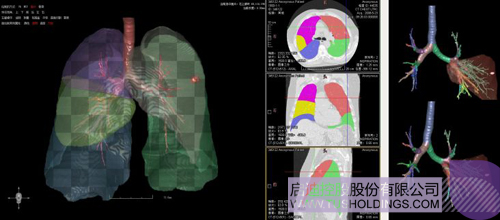

數字肺產品肺癌計算機輔助診斷

醫(yī)療影像智能分析是指運用人工智能技術、計算機視覺技術以及計算幾何技術對醫(yī)療影像進行自動分析,幫助醫(yī)生定位病癥、分析、跟蹤病情,并通過量化數據輔助醫(yī)生做出診斷,目前其旗艦產品“數字肺”已經覆蓋多種肺部疾病的早期檢測、診斷、跟蹤、術前規(guī)劃等完整的醫(yī)療流程。在臨床實踐中,超過80%的醫(yī)療數據來自醫(yī)療影像,這些影像數據通常需要專業(yè)醫(yī)生進行解讀,工作的重復性高、效率偏低。如果能夠運用智能影像分析技術,同時結合臨床表現以及既往病例進行全面分析,那么就可以大幅度提升影像診斷效率和準確性,讓專業(yè)醫(yī)生的寶貴時間集中在復雜病情的診斷和治療等環(huán)節(jié)。

數字肺——肺結節(jié)手術規(guī)劃系統